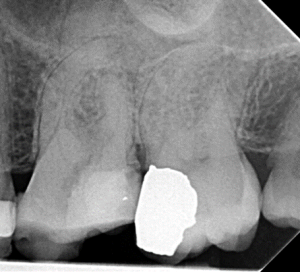

Root Canal / Retreatment

Apical Microsurgery / Apicectomy

Clinical Cases